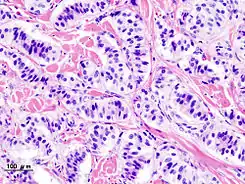

![]() Histopatología de tumor del páncreas endocrino (insulinoma). | ||